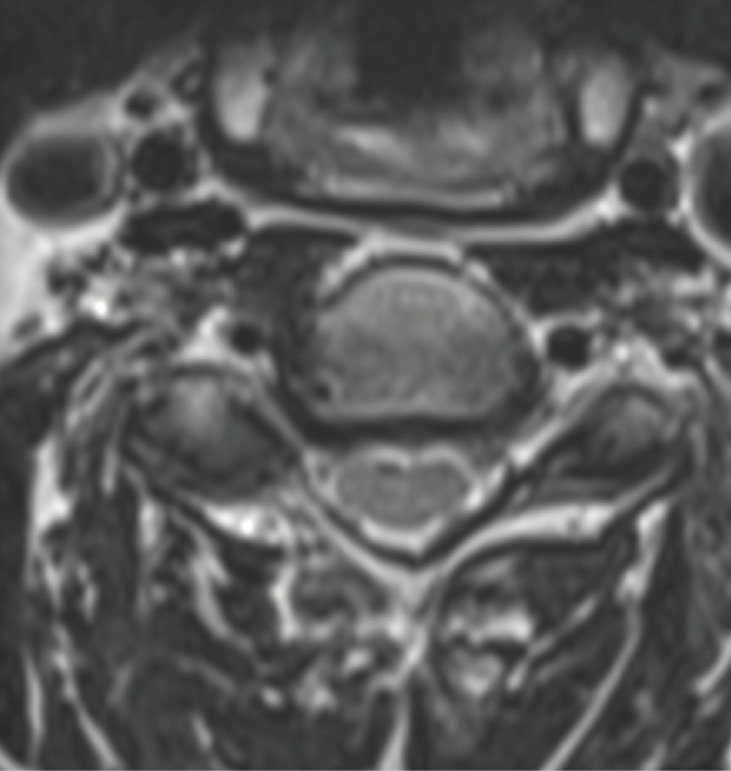

Pre-op MRI demonstrates partial disc height collapse and foraminal stenosis at C5-6 and C6-7.

Pre-op CT demonstrates right C5-6 uncovertebral joint osteophyte causing foraminal stenosis but minimal facet arthrosis.